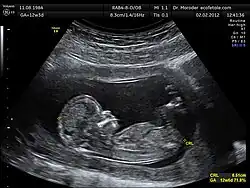

Акустика в медицине

Знания из различных разделов акустики широко используются как для диагностических целей (УЗИ и др.), так и для организации терапевтических процедур. В этом случае используются звуковые сигналы в широком диапазоне частот. Значительное внимание в медицинской акустике уделяется также изучению воздействия на организм человека звуков и вибраций различной интенсивности.